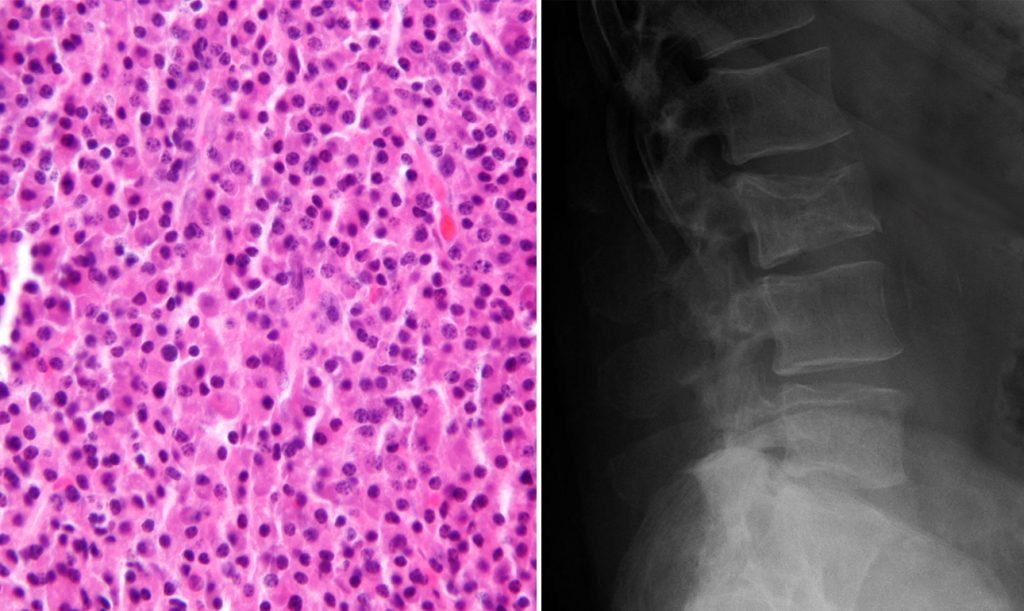

Το πολλαπλούν μυέλωμα είναι ένας ανίατος και απειλητικός για τη ζωή αιματολογικός καρκίνος, ο οποίος χαρακτηρίζεται από κλωνική υπερπλασία και καταστολή του ανοσοποιητικού συστήματος. Είναι μία σπάνια αλλά θανατηφόρα νόσος: περίπου 39.000 άνθρωποι διαγιγνώσκονται με πολλαπλούν μυέλωμα στην Ευρώπη, ενώ περίπου 24.000 ασθενείς καταλήγουν από τη νόσο ετησίως. Η διάμεση ηλικία διάγνωσης στην Ευρώπη είναι τα 65-70 έτη. Στην Ευρώπη, ασθενείς με καλή φυσική και κλινική κατάσταση, θεωρούνται κατά κανόνα κατάλληλοι για αυτόλογη μεταμόσχευση αρχέγονων αιμοποιητικών κυττάρων.